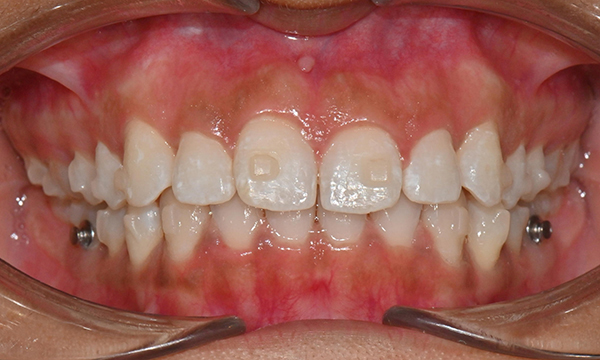

치아 상태는 어땠냐면요:

위아래 앞니 사이에 공간이 벌어져 있었어요.

앞니가 삐뚤빼뚤한 덧니도 있었죠.

윗니와 아랫니가 너무 깊게 맞물리는

과개교합이 있었어요.

왼쪽 아래 작은어금니가 90도 돌아가 있었는데,

이로 인해 왼쪽 치아 배열과 교합이 좋지 않았죠.

초진시 구내사진 (2025. 3.31)